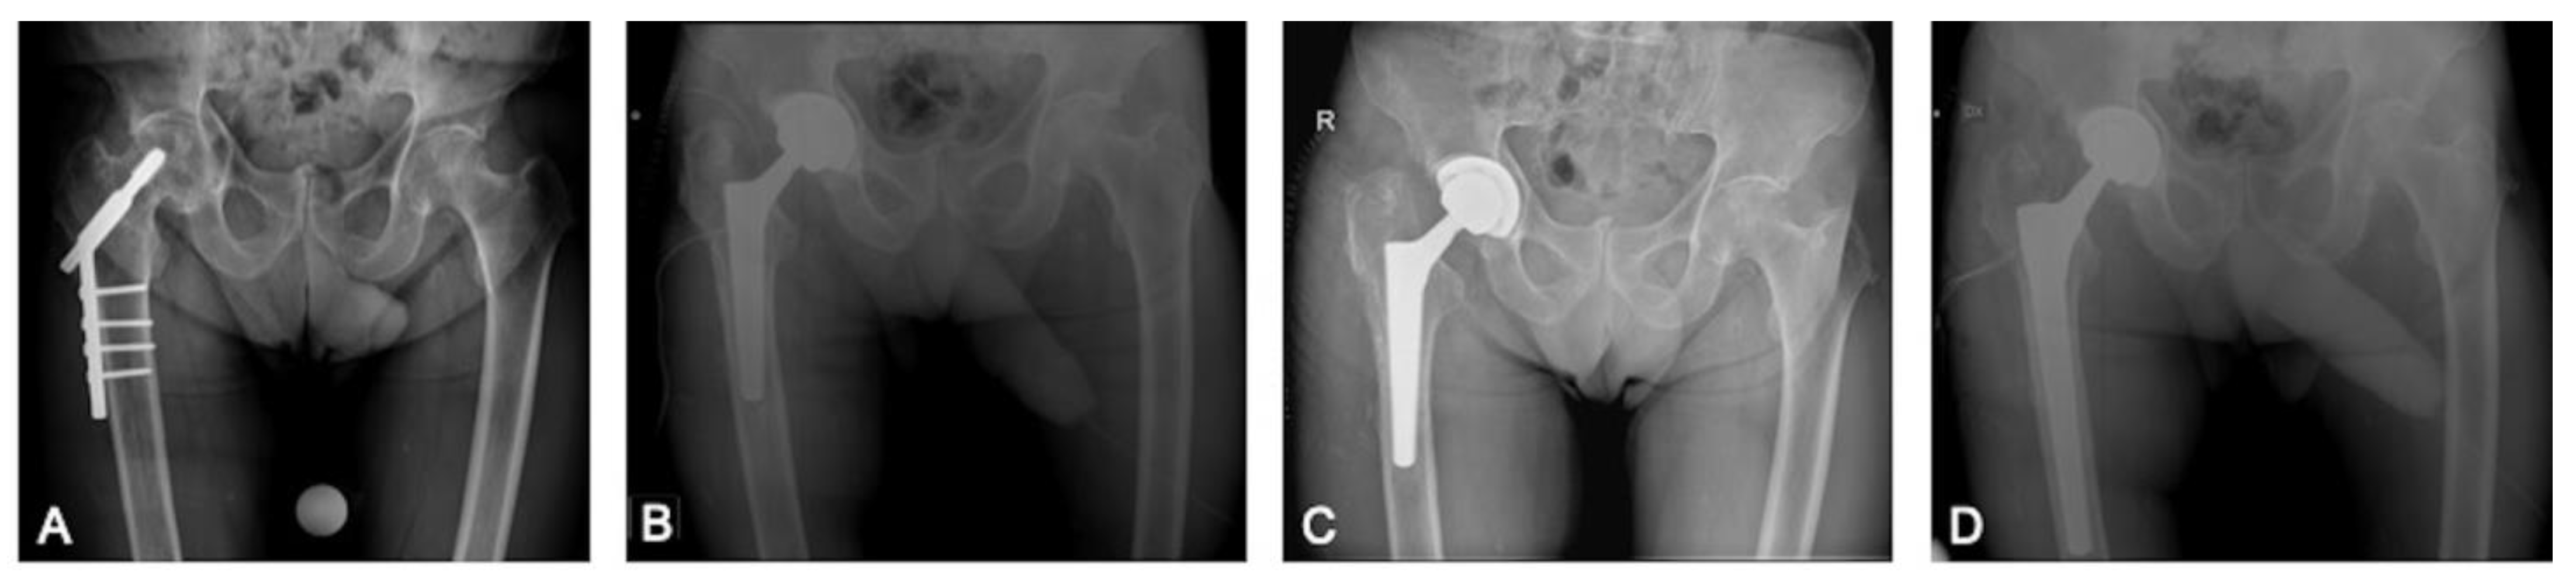

2.1. Surgical Procedure